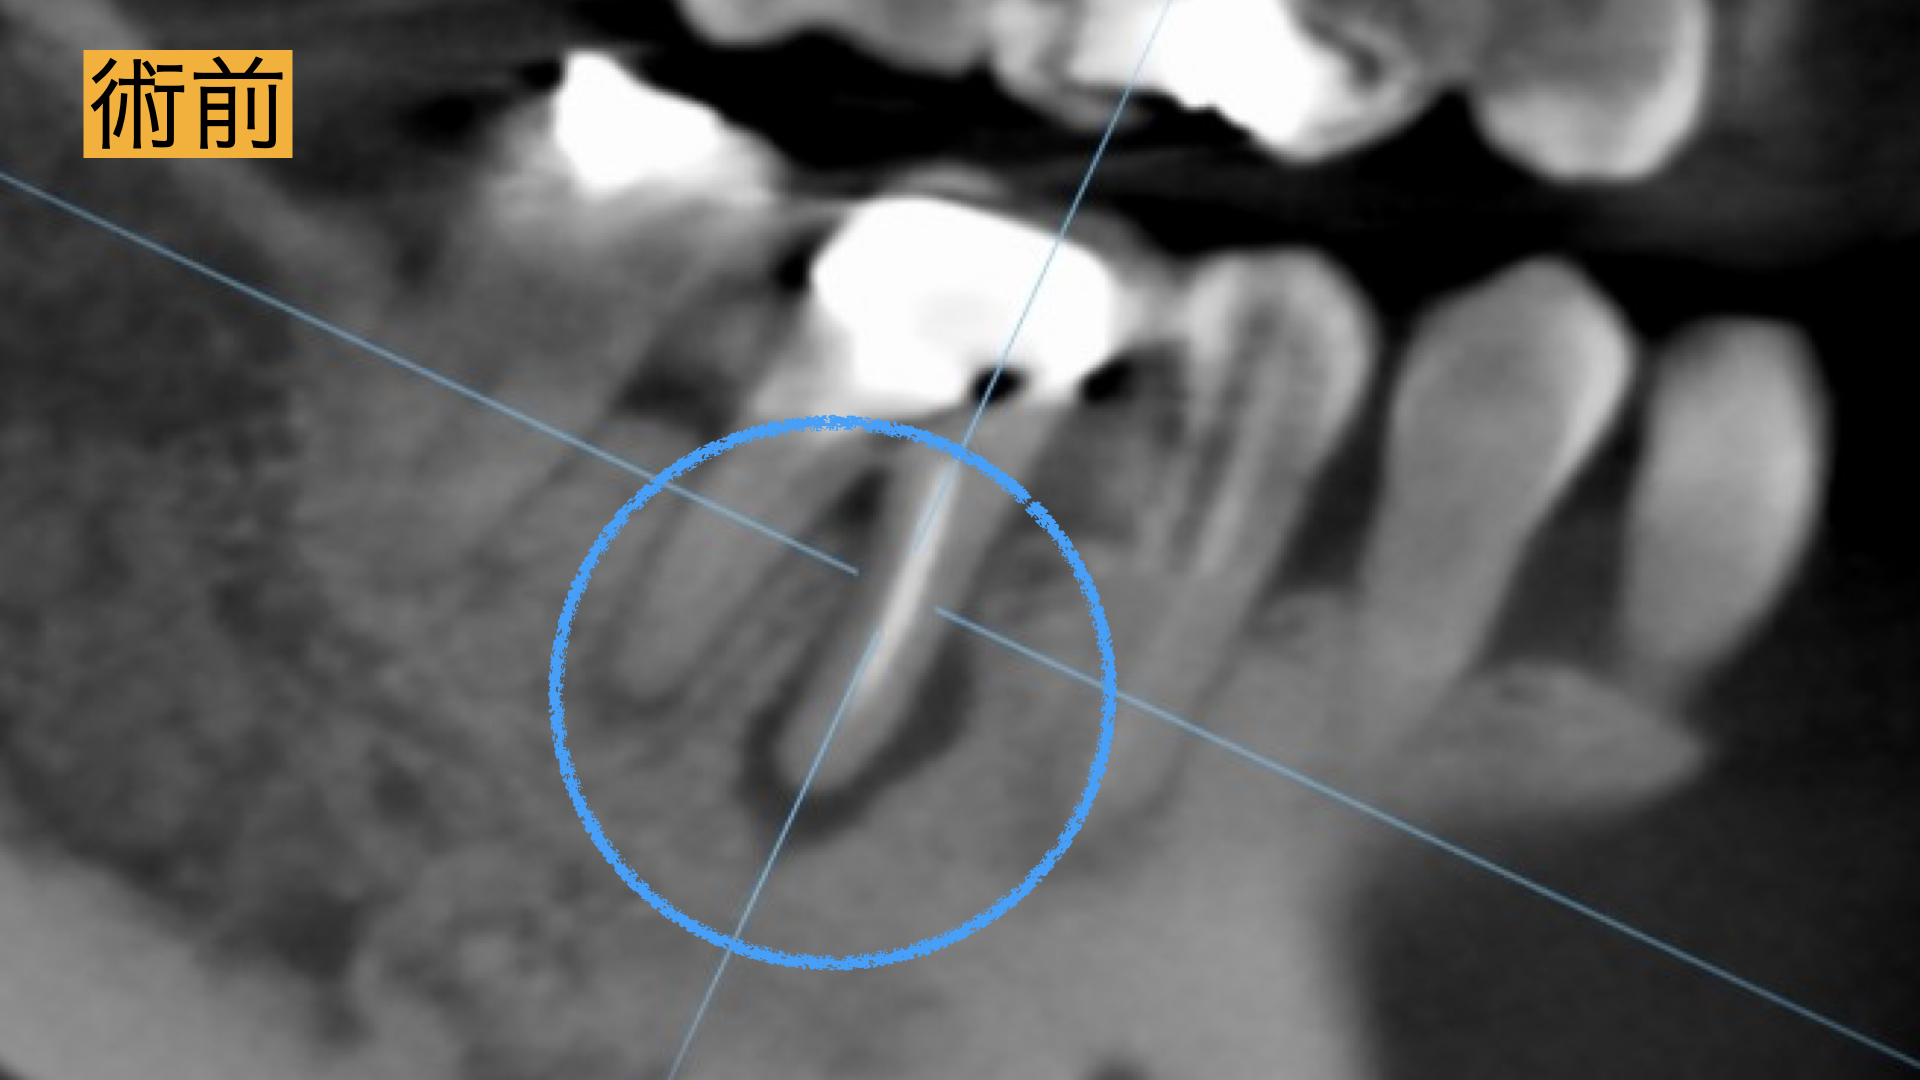

3D診断(CT)

歯科用CTは3次元の立体画像で診断することが可能です。通常のXrayは2次元の写真のため、 根管治療において複雑な根管形態を正確に把握できません。 CTでの根管形態の把握は、根管治療において必須です。